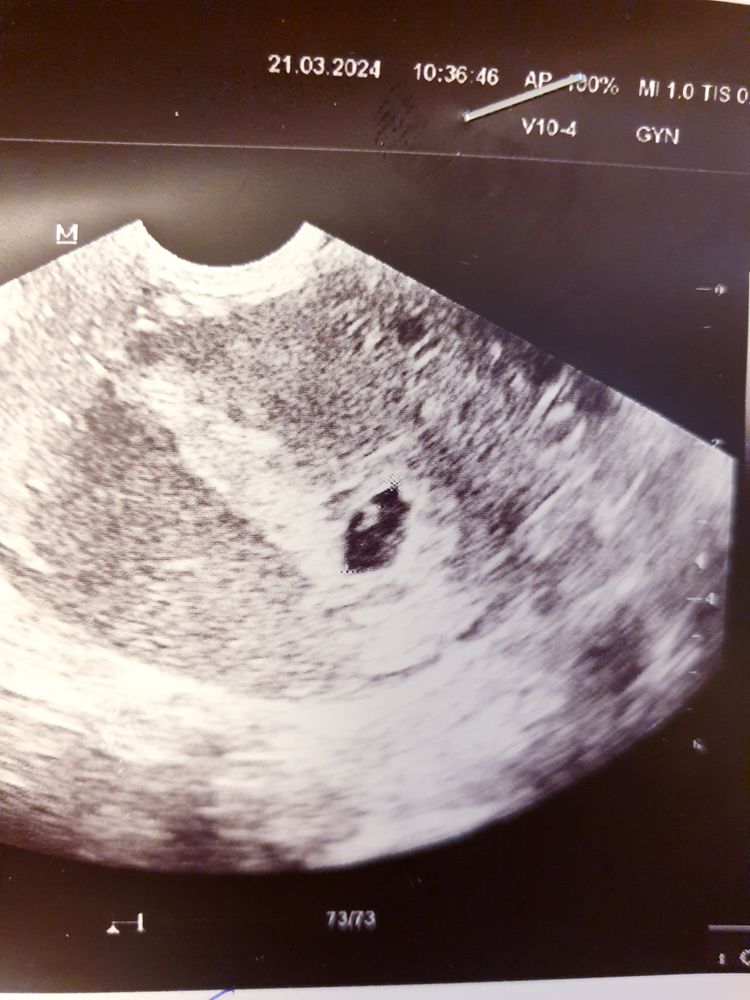

Снимок узи

По снимку похоже что эмбрион есть,но я не профи в УЗИ, желточный мешок без эмбриона он круглый,в у вас форма другая и очень напоминает эмбрион,вот к примеру у меня жм без эмбриона Изображение

Мне почему то тоже кажется, что видно эмбрион.

Вероника, слева наверху,верно?

Галя, ну как бы да. А жм я не нашла. Но я не врач🤷

Вероника, очень плохое качество снимка, в живую видно намного лучше.Мне вообще кажется,что я вижу 2 жм🙈

Галя, вроде нашла его, справа от предполагаемого эмбриона...